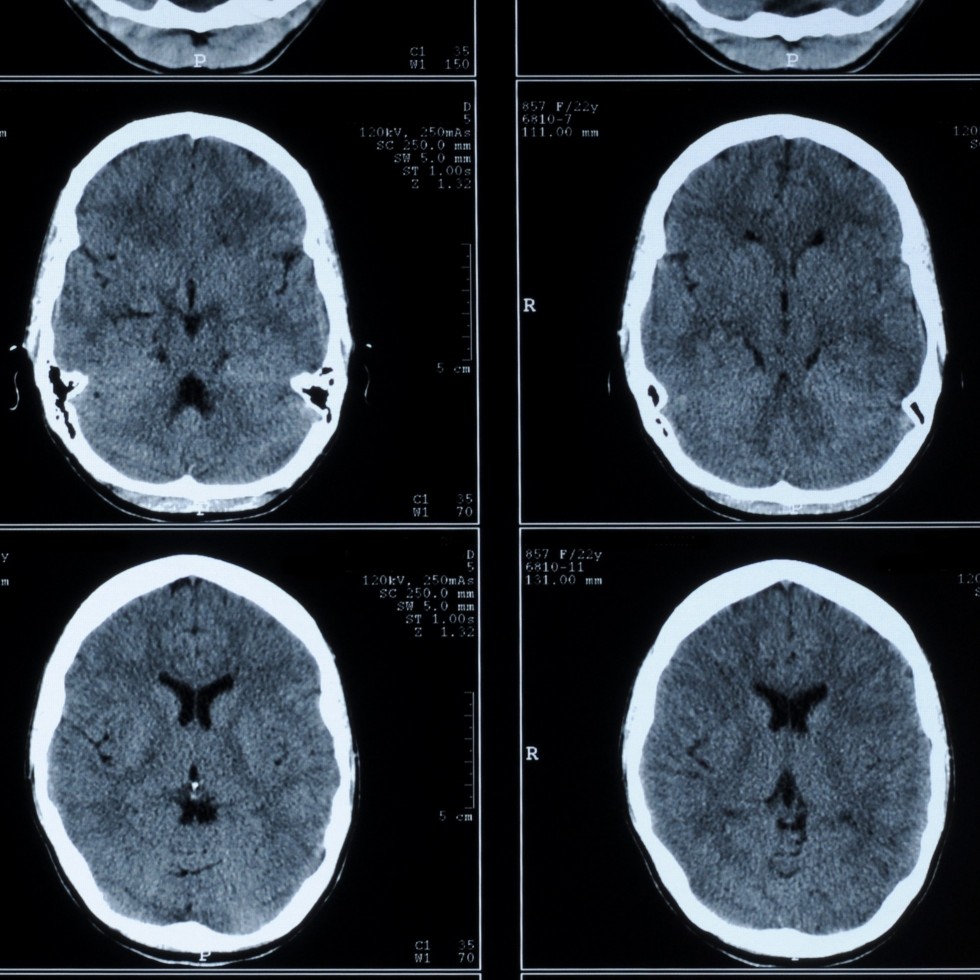

Head CT

A CT scan is a type of scan that uses special X-ray equipment to obtain images from all angles of the body. It then joins the images together to show a cross-section of body tissues and organs. The scan provides detailed information on the scanned part of the body.

During the scan you will lie on a moving table. A rotating device spins around your body creating a beam of X-rays. A detector takes snapshots of the beam after it passes through your body and a powerful computer program then processes the images and displays them in different ways for examination. The technician will communicate with you throughout the procedure, but will need to leave the room briefly to run the computer. A radiologist then reviews the images to look at the area in question.